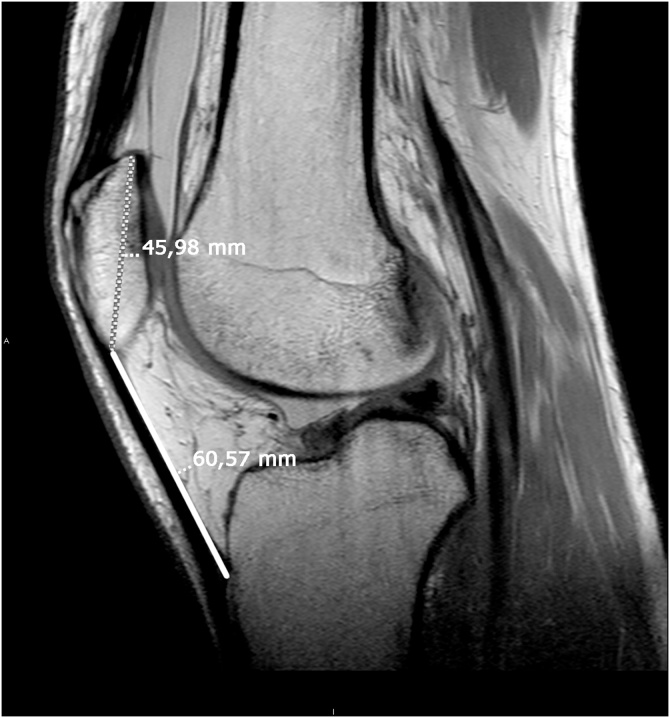

Fig. 5.

Sagittal knee MRI image in T1 sequence demonstrating patella alta (Insall-Salvati index of 1.5).